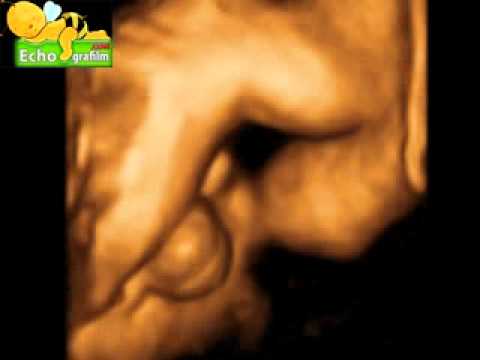

Echographie 3D sexe masculin, c'est un garcon